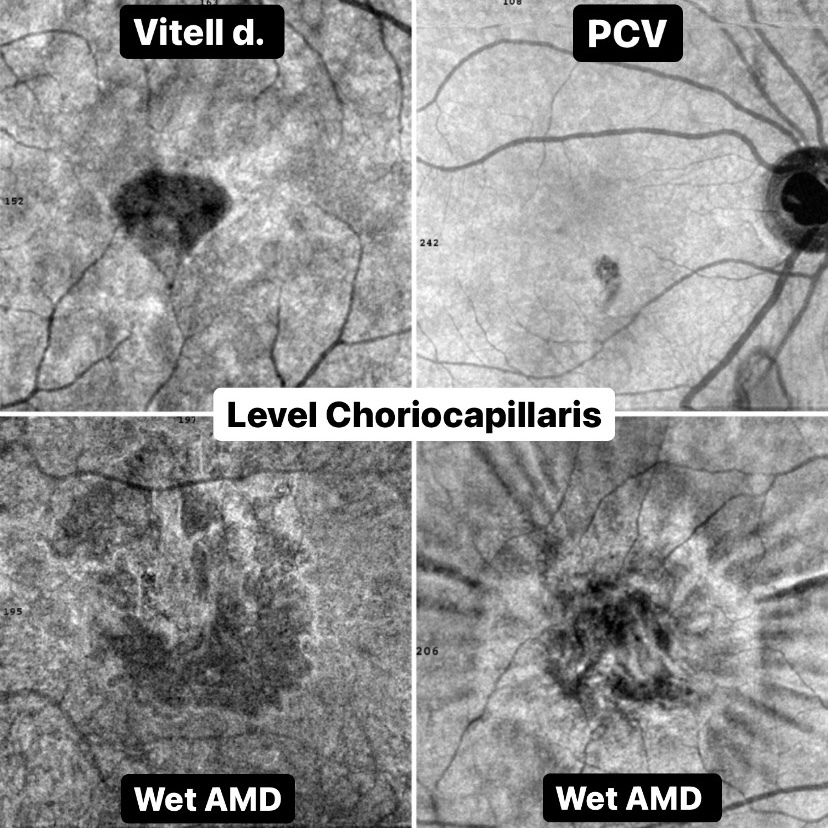

Окончив курс "Оптическая когерентная томография.НАЧАЛО" мы обрели умение видеть признаки патологии на сканах OCT.

Настало время усложняться и углубляться!

ЭТОТ КУРС ПОСВЯЩЕН:

1. Дифференциальной диагностике заболеваний заднего отрезка глаза;

2. Умению видеть признаки стадий и активности заболеваний;

3. Умению формировать курсы лечения и прогнозировать перспективу для пациента.

Настало время усложняться и углубляться!

ЭТОТ КУРС ПОСВЯЩЕН:

1. Дифференциальной диагностике заболеваний заднего отрезка глаза;

2. Умению видеть признаки стадий и активности заболеваний;

3. Умению формировать курсы лечения и прогнозировать перспективу для пациента.

Это курс для специалистов, имеющих четкое представление о многообразии патологий заднего отрезка глаза и желающих научиться быстро и точно дифференцировать эти заболевания по такому, казалось бы НЕПАТОГНОМОНИЧНОМУ признаку, как ОТЕКИ СЕТЧАТКИ.

А самое главное, научиться строить план лечения конкретного пациента и давать прогноз этому лечению.

Весь этот курс, как и все предыдущие тренинги проекта STROMASCHOOL, имеют лишь одну принципиальную цель - донести до Вас, коллега, важную для офтальмологического труда информацию, привести Вас к важным практическим выводам и сделать так, чтобы даже если перед Вами нестандартная картина заболевания и Вы прежде такого не видели, Вы не на секунду не застопорились, а наоборот начали ДУМАТЬ, клинически думать, и смогли в итоге сделать диагностическое предположение и поставить диагноз.

А уж имея диагноз составить схему терапии труда не составит!